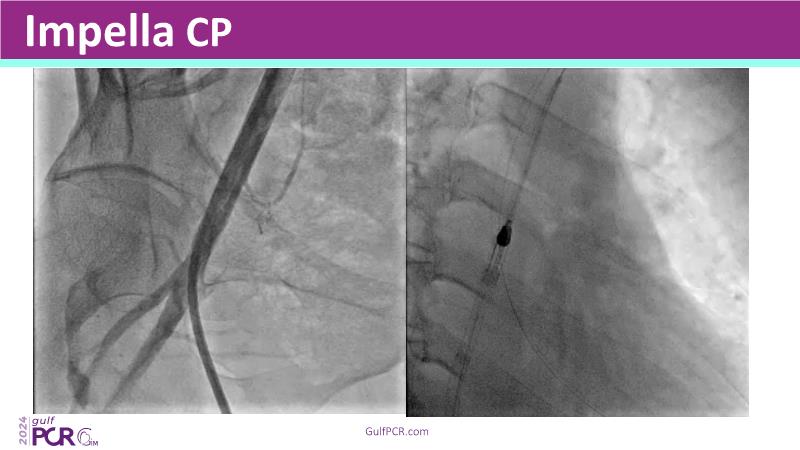

This session highlights the essential role of mechanical circulatory support (MCS) in managing high-risk PCI and AMI-related cardiogenic shock. Explore case-based discussions on device selection, hemodynamic impact, and evidence-based strategies to optimize outcomes in complex scenarios.

- To learn the indications and choices for MCS in high-risk PCI and AMI-cardiogenic shock